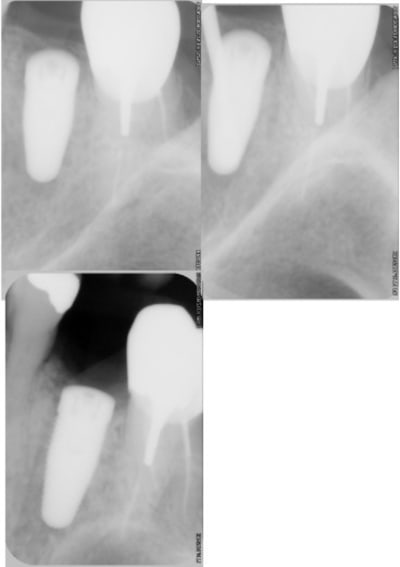

> encore un petit exemple de mise en vitrine réalisée hier matin...

> le résumé en vision "radio".

j'ai mis un XIVE de chez densply D4.5 L9.5 et un moignon provisoire esthétic cap ovale pour un implant de diamètre 3.8.

j'obtiens ainsi un plat-form switching que je trouve nécessaire pour une bonne cicatrisation.

l'os vestibulaire était fin mais je n'y ais pas touché, j'ai comblé le vide avec un peu de béta TCP.

un cas d'infection apicale (patient avec 1.10 glycemie)ouverture, curetage prudent, AB, et controle ce jour (à 2 mois), plus aucune trace à l'examen, son à l'impact clair et semble t il radio ok.

> le résumé en vision "radio".